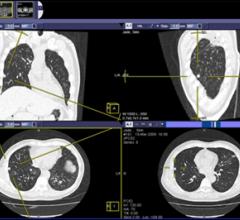

For more information about our cardiology solutions, visit www.changehealthcare.com/connectedradiology